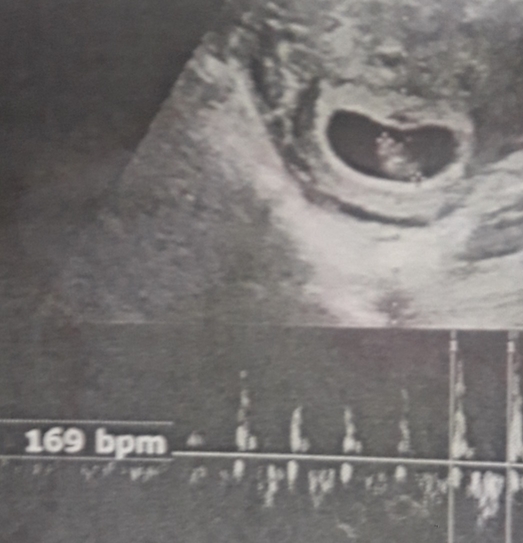

سلام نیلوفرجان ممنون میشم نظرت راجب این سونو قلب بگی

من از روی سونوی قلب و طبق نظریه ی رمزی احتمال میدم...

اگه عکس سونوی قلب رو داری بفرست ببینم...

این عکس عزیزم

بفرست گلم فقط جهت سرگرمی بهش نگاه کن چون خطا هم زیاد دیدم از این نظریه رمزی...